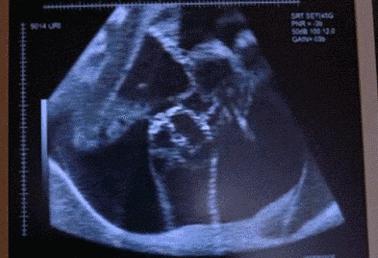

双胞胎,38周+5,胎心低。产妇有轻微心脏病。